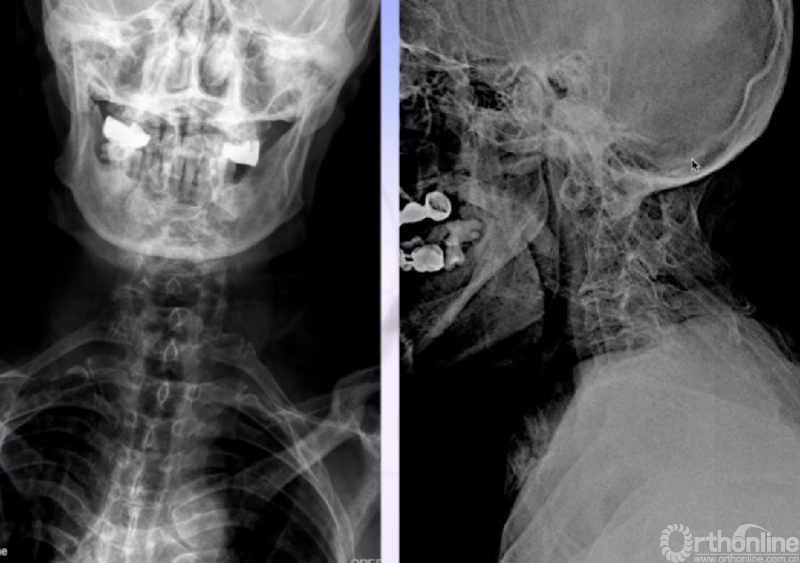

X线正、侧位

枕颈融合术后21年,术后神经功能无明显改善,但症状稳定;3年前出现四肢麻木、乏力加重,行走不稳;1周前出现气促、声音低、吞咽困难。

由急诊入院,二便无殊;查体:半卧(坐、立受限)、吸氧;四肢浅感觉减退、肌力4级,腱反射+++,病理征+。